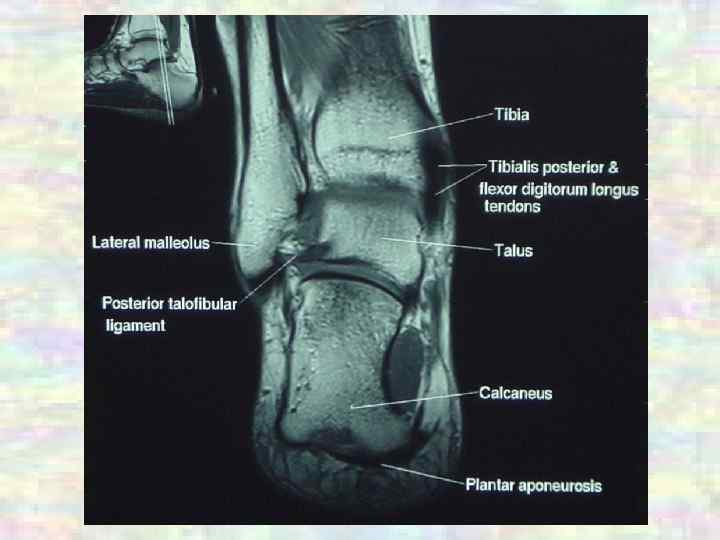

СУСТАВЫ Суставы нижней конечности Межплюсневые ü Подтаранный: цилиндрический, одноосный, малоподвижный (скольжение) ü Таранно-пяточно-ладьевидный: шаровидный, многоосный, малоподвижный (супинация, пронация) ü Межплюсневые: плоские, малоподвижные (супинация, пронация) ü Плюснефаланговые: эллипсоидные, двухосные (сгибание, разгибание – общий объем около 90°; приведение, отведение, движение большого пальца) ü Межфаланговые суставы стопы: блоковидные, одноосные (сгибание, разгибание, движения II-IV пальцев)